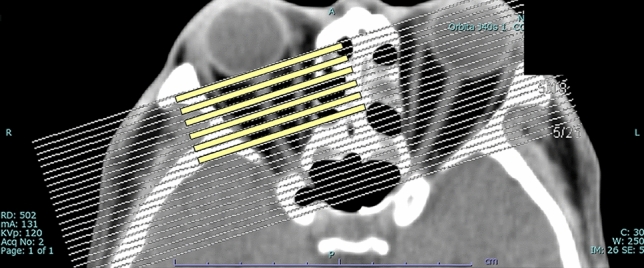

Extraocular muscles were analyzed with orbital images obtained using a whole-body CT system (SOMATOM Definition AS+; Siemens, Erlangen, Germany) without contrast. Axial scans were obtained at an angle of − 10° to − 15° to the orbitomeatal line, and coronal scans in a paraxial plane 90° to the orbital axis were reconstructed from the axial scans (slice thickness, 2 mm). We measured the diameter of all rectus muscles shown on six slices from the globe’s posterior margin to the orbital apex (Fig. 3). The maximum diameter was defined as the thickest diameter of each muscle on the six slices. The spindle-like spreading of the rectus muscles without tendon involvement was identified morphologically as EEM23. Diameters of the superior, inferior, medial, and lateral rectus muscles were measured on coronal scans. The inferior and superior oblique muscles were excluded because their course is oblique to the coronal plane.

Figure 3.

Coronal scans in a paraxial plane 90° to the orbital axis were reconstructed from the axial scans (a). Sequential six slices (2-mm thickness) from the posterior margin of the globe toward the orbital apex on the coronal scans were used (b).